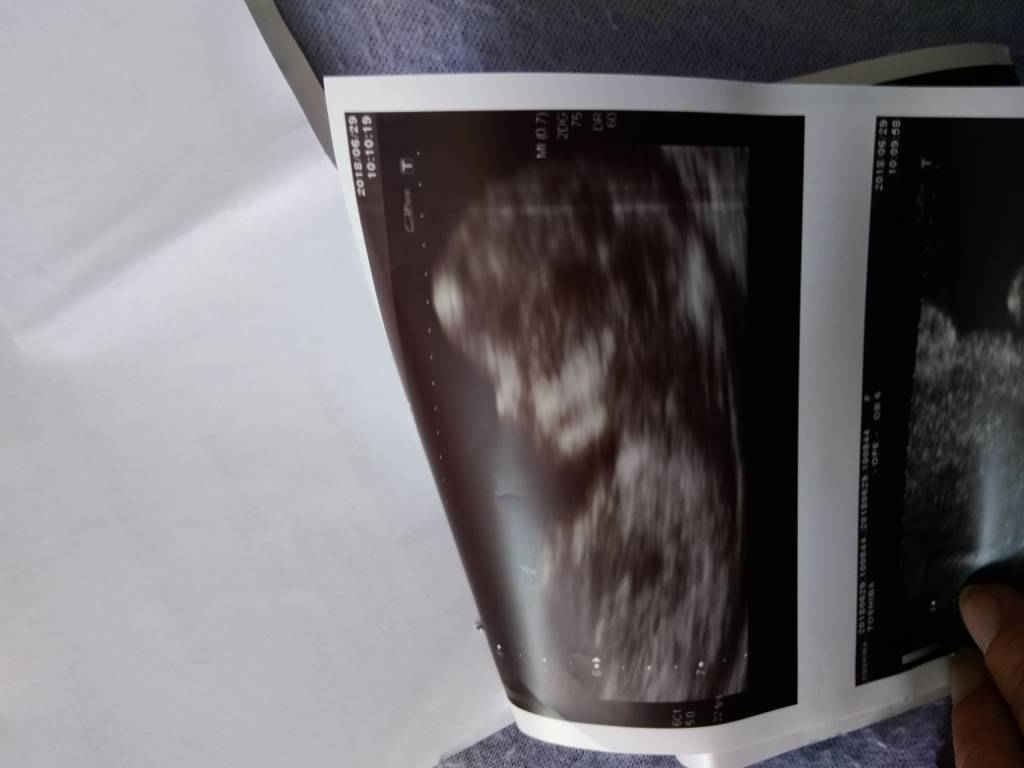

Hej dziewczyny,ja już po.. badaniu na NFZ,lekarz okropny gbur ,nawet nie mogłam na monitor patrzeć i się odezwać ..serce mi waliło bo nic nie wiedziałam, ale najważniejsze że wszystko ok ,dziś wg OM 12+ 1, w poniedziałek idę naszczescie prywatnie i będę miała też 4 d ,więc popatrze na dzidzię i.moze płeć poznamy ...

Hej dziewczyny,ja już po.. badaniu na NFZ,lekarz okropny gbur ,nawet nie mogłam na monitor patrzeć i się odezwać ..serce mi waliło bo nic nie wiedziałam, ale najważniejsze że wszystko ok ,dziś wg OM 12+ 1, w poniedziałek idę naszczescie prywatnie i będę miała też 4 d ,więc popatrze na dzidzię i.moze płeć poznamy ...Zobacz załącznik 872044Zobacz załącznik 872045

A dzidzia prześliczna!

Śliczne dzieciątko[emoji6]powiem wam że lekarz-gbur potrafi zepsuć humor,ale place i spróbowałby być niemiły[emoji16]

Dziękuje [emoji16]Wiecie co taka ciekawostka.. własnie sobie sprawdziłam i mój drugi syn z którym miałam identyczny termin porodu ,,miałam robione dokładnie tego samego dnia robione USG i byl co do.mm taki sam - taka sama długość ... wszystko takie samo. Urodził się 10 dni przed terminem z wagą 4 kg ciekawe czy wszystko się powtórzy.